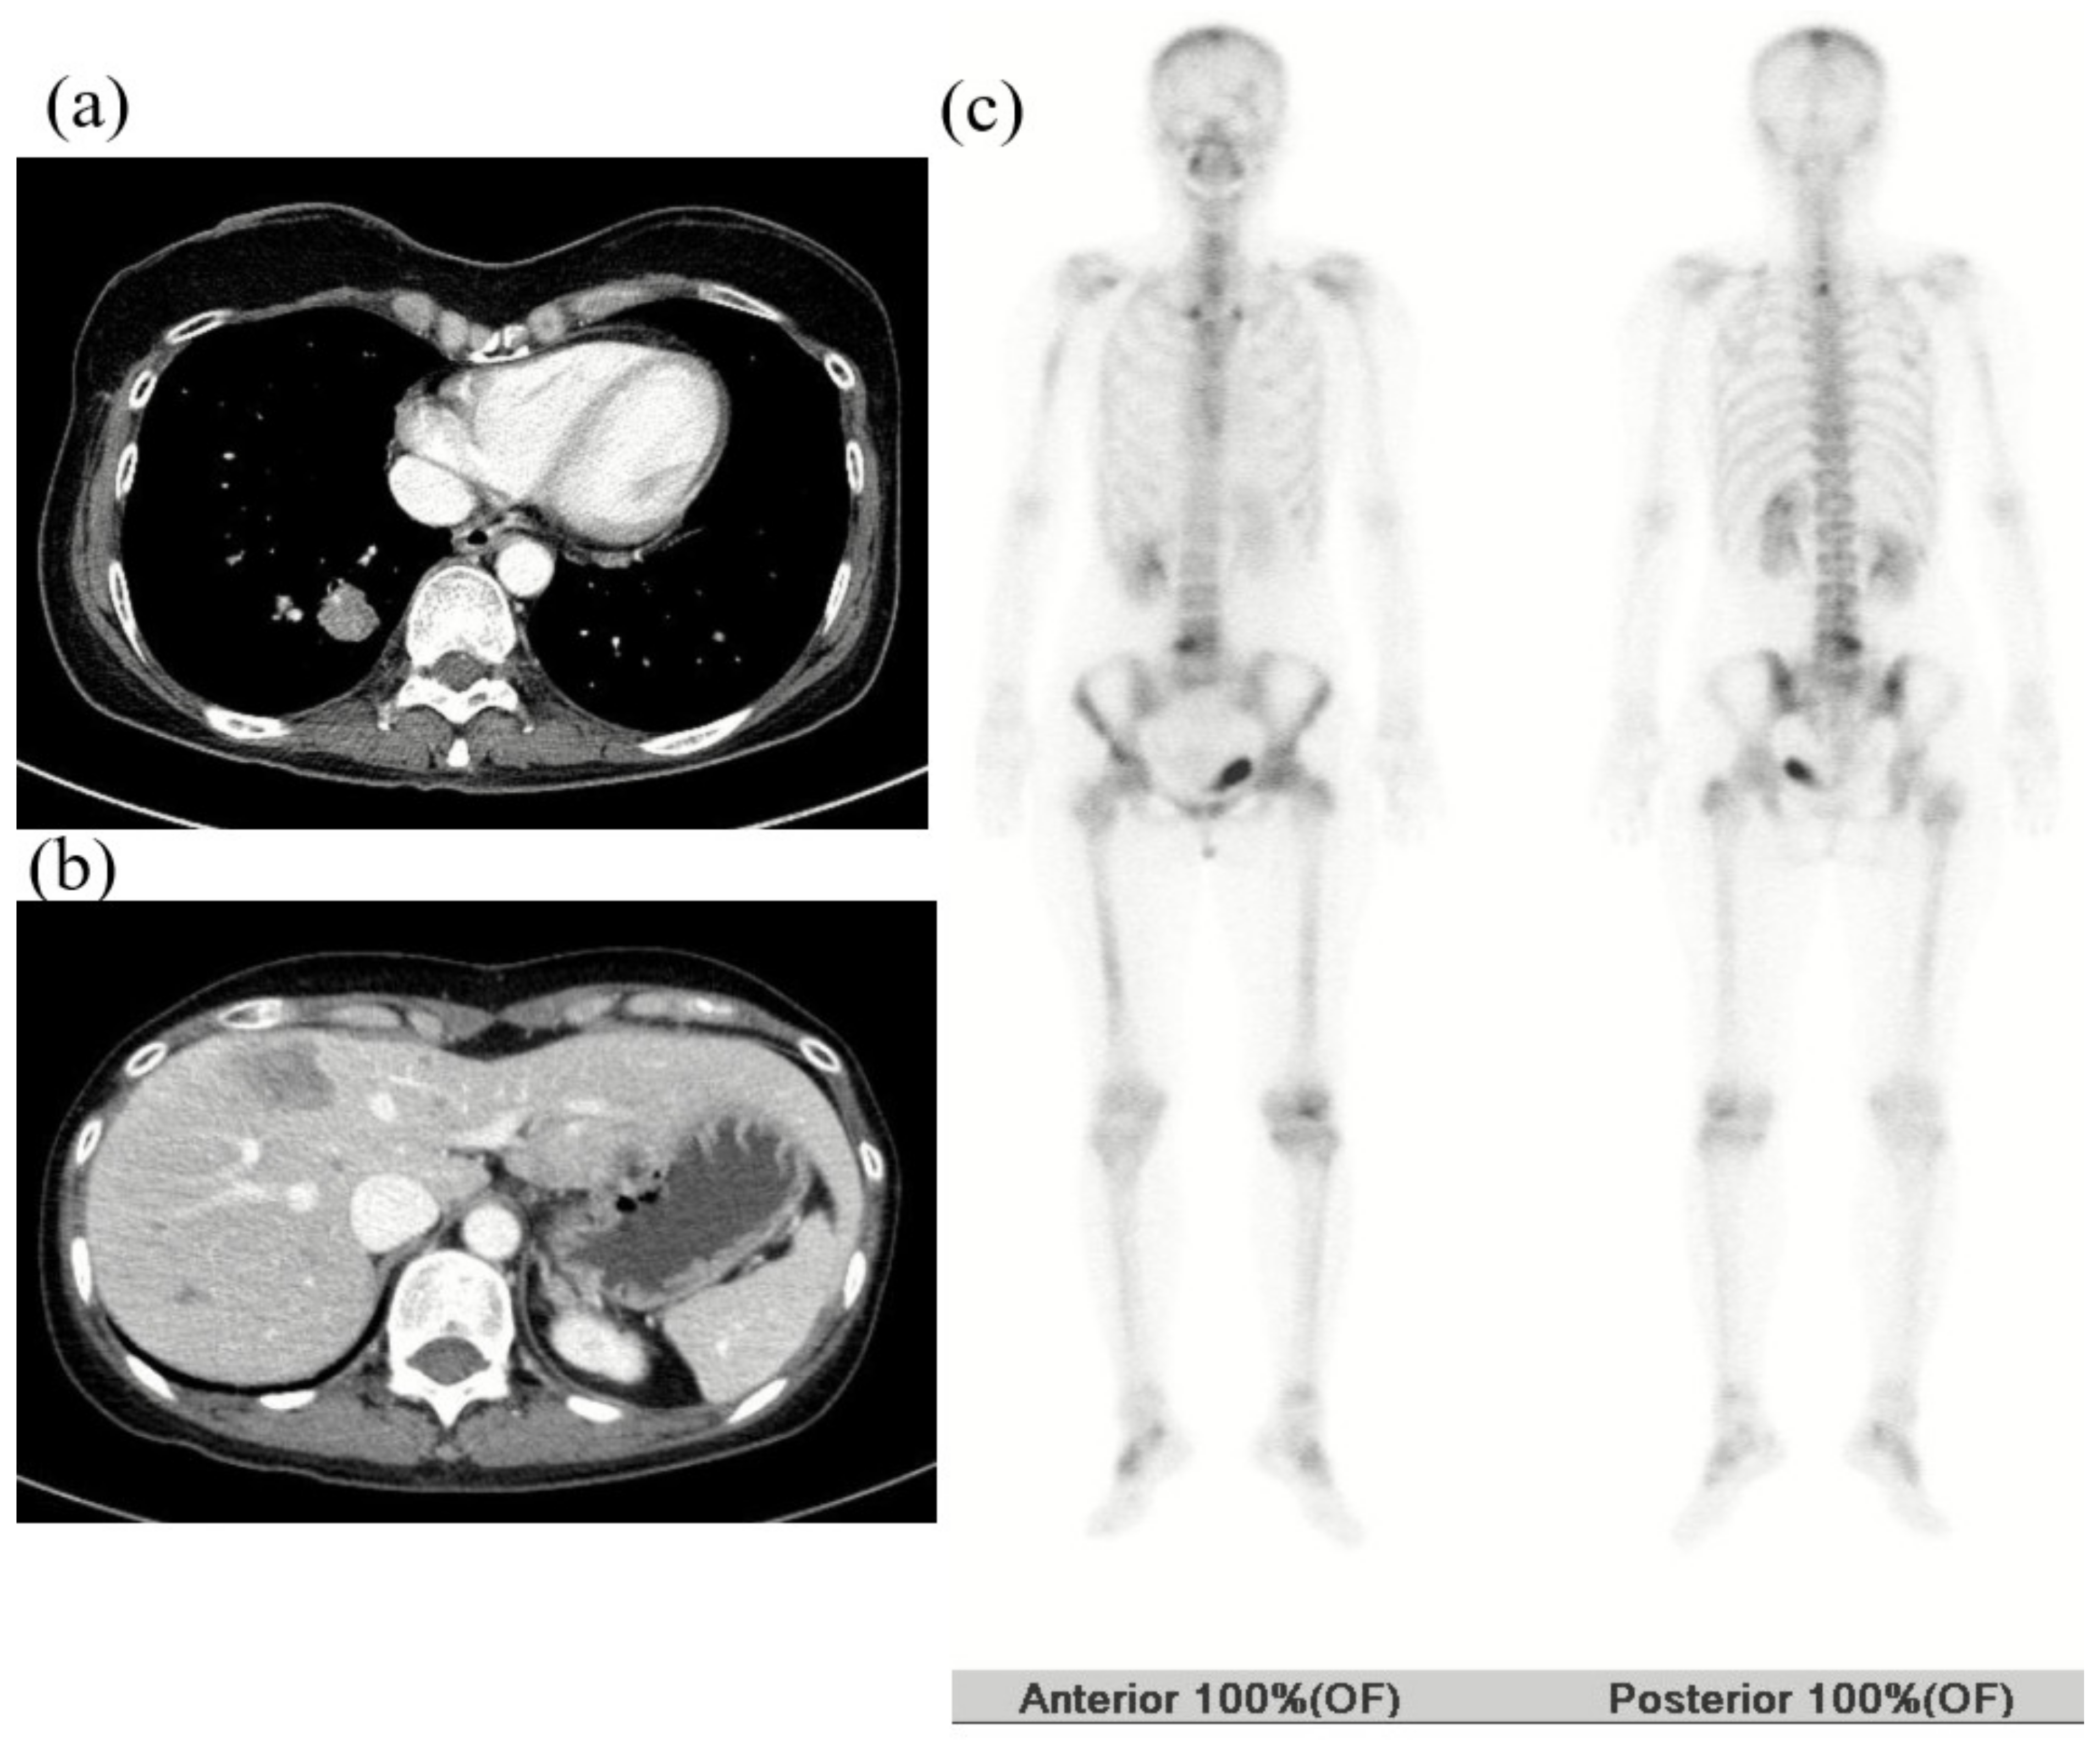

2.2. First Case

2.3. Second Case

2.4. Third Case

2.5. Fourth Case